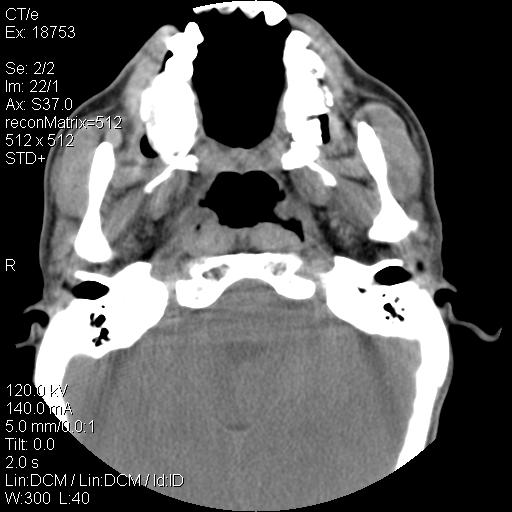

标题: CT21693:男 58岁 右侧咽部疼她2天余 PE:右侧扁桃体肿大 压痛 [打印本页]

标题: CT21693:男 58岁 右侧咽部疼她2天余 PE:右侧扁桃体肿大 压痛

喉部新生物,喉癌可能大,建议喉镜取组织活检。

右化脓性扁桃体炎症伴咽后壁脓肿形成.